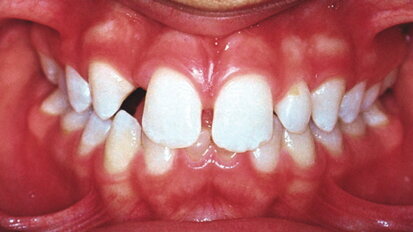

Conservative smile design for the general dentist

This article discusses the advantages of short-term anterior tooth alignment using the Inman Aligner system, particularly for general dentists. The article ...